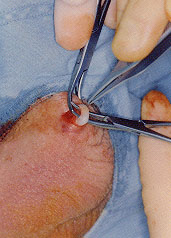

The doctor then feels for the vas deferens in the scrotum, locates it and

brings it close to the surface of the skin in the midline. Some local

anesthetic is then injected first

into the skin and then around the

vas itself. This anesthetic takes

effect very quickly so that any

discomfort is minimal.

Once the

area is numb, a special instrument

is used to make a small opening in

the scrotum. A loop of the vas

deferens is then lifted out through

this small opening, is clamped in

two spots, and a portion of the

tube removed.

The cut ends are

then sealed with cautery and are

tied off with suture material.